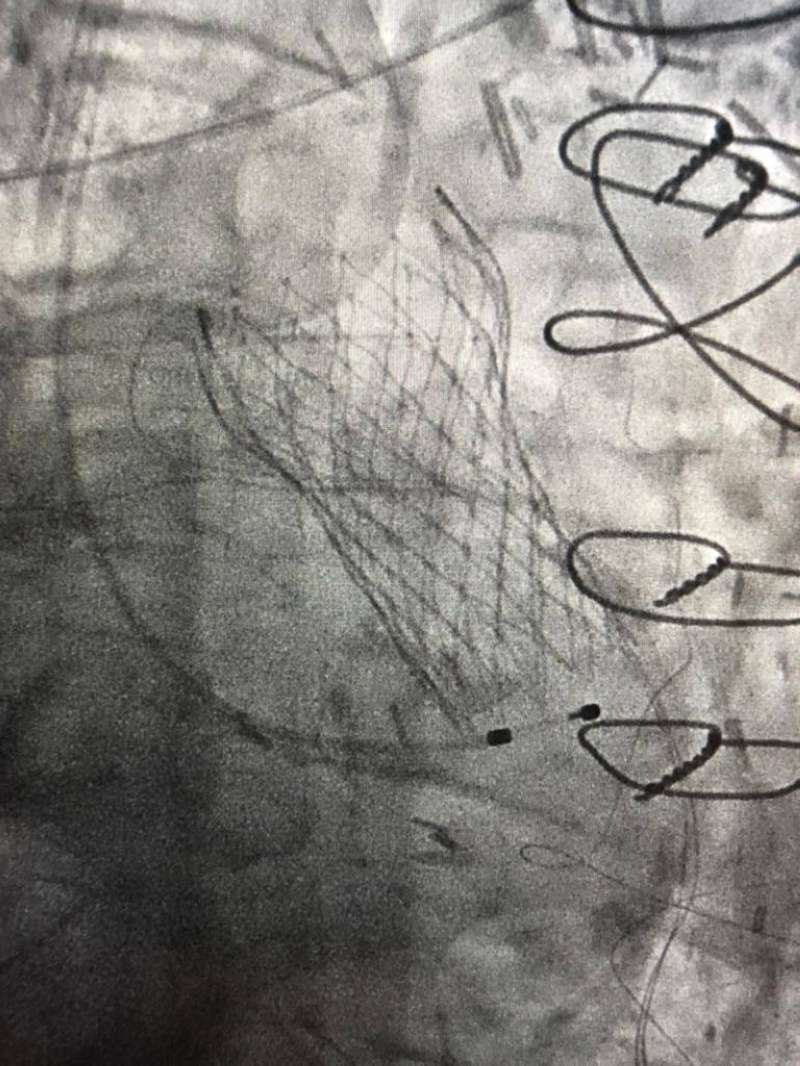

في إنجاز طبي غير مسبوق بدولة الكويت ووسط اجراءات طبية دقيقة نجح فريق طبي في مركز صباح الأحمد للقلب يضم استشاري القلب الدكتور نادر عيسى العسعوسي واختصاصي أول قلب الدكتور أحمد سعيد طه في إجراء عملية تبديل صمام أورطي (TAVI) عن طريق القسطرة لمريض يبلغ من العمر 101 سنة.

ويعتبر ما حدث إنجازاً غير مسبوق ليس من حيث درجة تعقيد العملية أو عمر المريض المتقدم ولكن لإجراء تبديل الصمام بدون استخدام صبغة للحفاظ على وظائف الكلى وهو ما يمثل أيضا اجراء طبيا غير مسبوق، حيث يتم في مثل هذه الحالات استخدام الصبغة لتسهيل إجراء عملية تبديل الصمام التي زاد من درجة صعوبتها و تعقيدها معاناة المريض من ضيق شديد بالصمام الأورطي وفشل عضلة القلب وقصور مزمن بشرايين القلب ووظائف الكلي، وتمدد بالشريان الأبهر في منطقة البطن (abdominal aortic aneurysm with mural thrombus).

وقد استغرقت العملية نحو ساعة وسط إجراءات طبية دقيقة بالنظر لظروف الحالة وتحدياتها بالغة التعقيد؛ حيث بذل فيها الفريق الطبي جهوداً تستحق التقدير وجديرة الثناء، وقد تماثل المريض للشفاء وأصبح بحالة جيدة مستقرة.